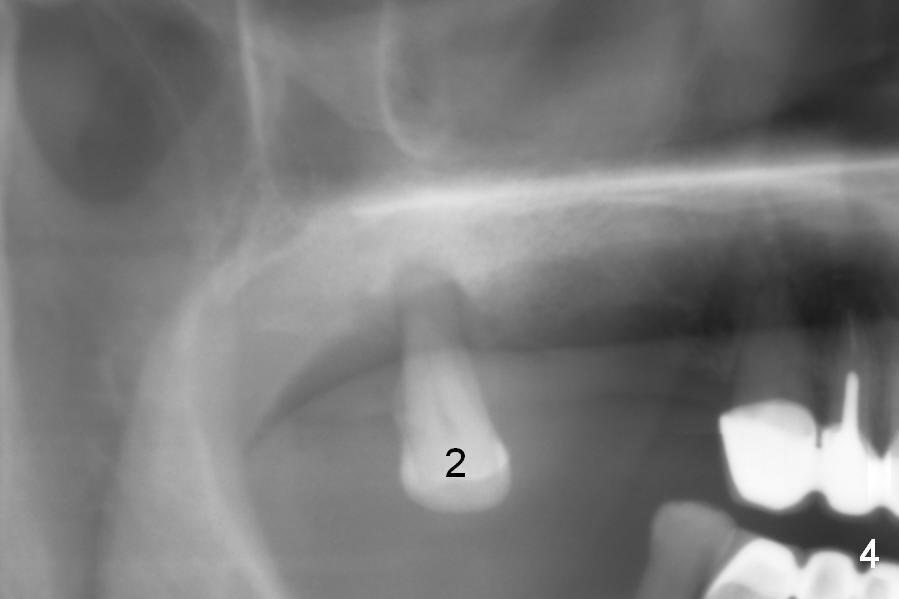

The furcation of the upper 2nd molars is variable. For example, the buccal roots of the 2nd molar may be fused (Fig.4-6). The septum may be destroyed due to infection such as in this case (Fig.4). An immediate implant could be placed in the septum or the buccal and palatal sockets, depending upon the integrity of the buccal and palatal plates.